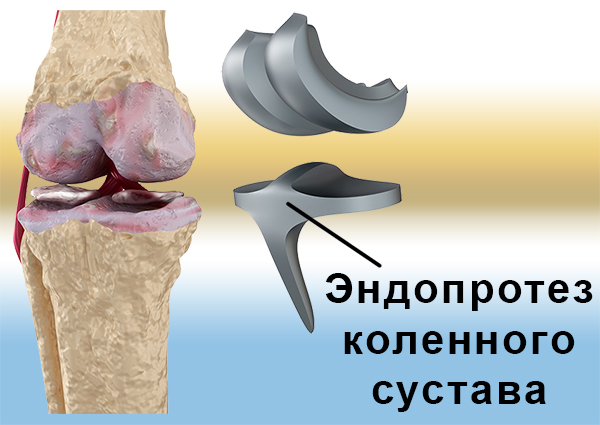

Фотографии и примеры протезирования коленного сустава